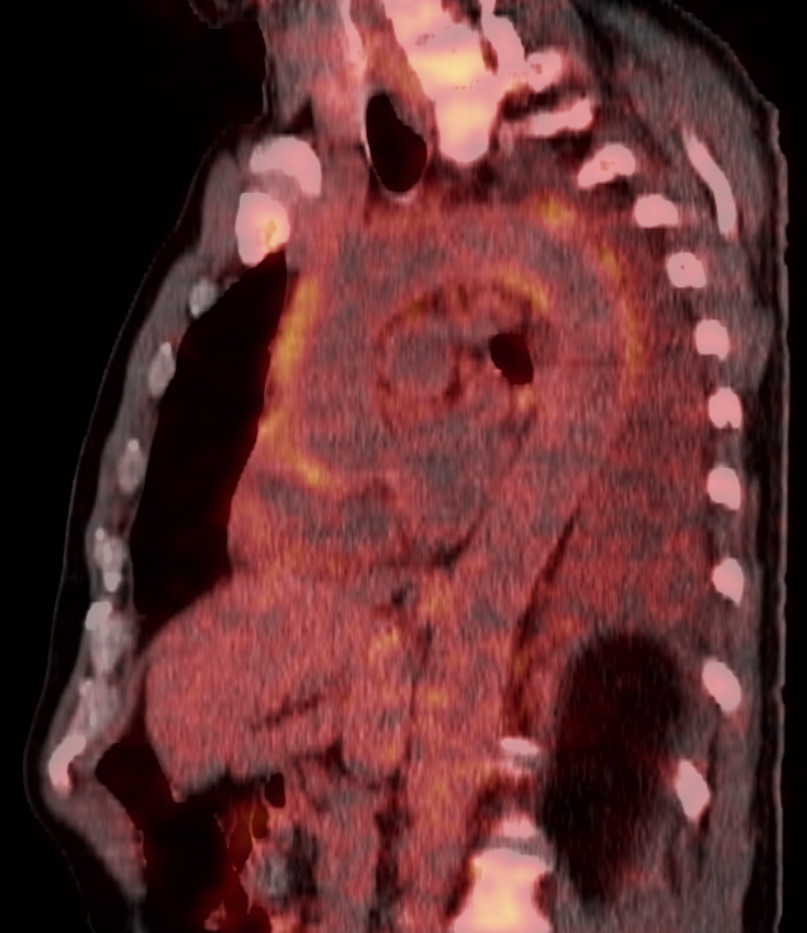

PET-CT-undersøkelse med ¹⁸F-fluordeoksyglukose (¹⁸F-FDG) utført ved innleggelsen viste økt opptak av ¹⁸F-fluordeoksyglukose i torakalaorta, buekaravganger og perikard (figur 1).

Det var også økt opptak av ¹⁸F-fluordeoksyglukose i benmarg og lymfeknuter, som ble vurdert å være reaktive forandringer. I tillegg ble det funnet et infiltrat i venstre lunges underlapp og pleuravæske (figur 2).

Tilstanden ble oppfattet som ekstrakraniell kjempecellearteritt. Diagnosen ble stilt på bakgrunn av følgende symptomer og funn: redusert allmenntilstand, smerter i brystet, hodet og kjeveledd, veggfortykkelse i venstre arteria subclavia, økt opptak av ¹⁸F-fluordeoksyglukose i store blodårer og forhøyede verdier av akuttfasereaktanter.